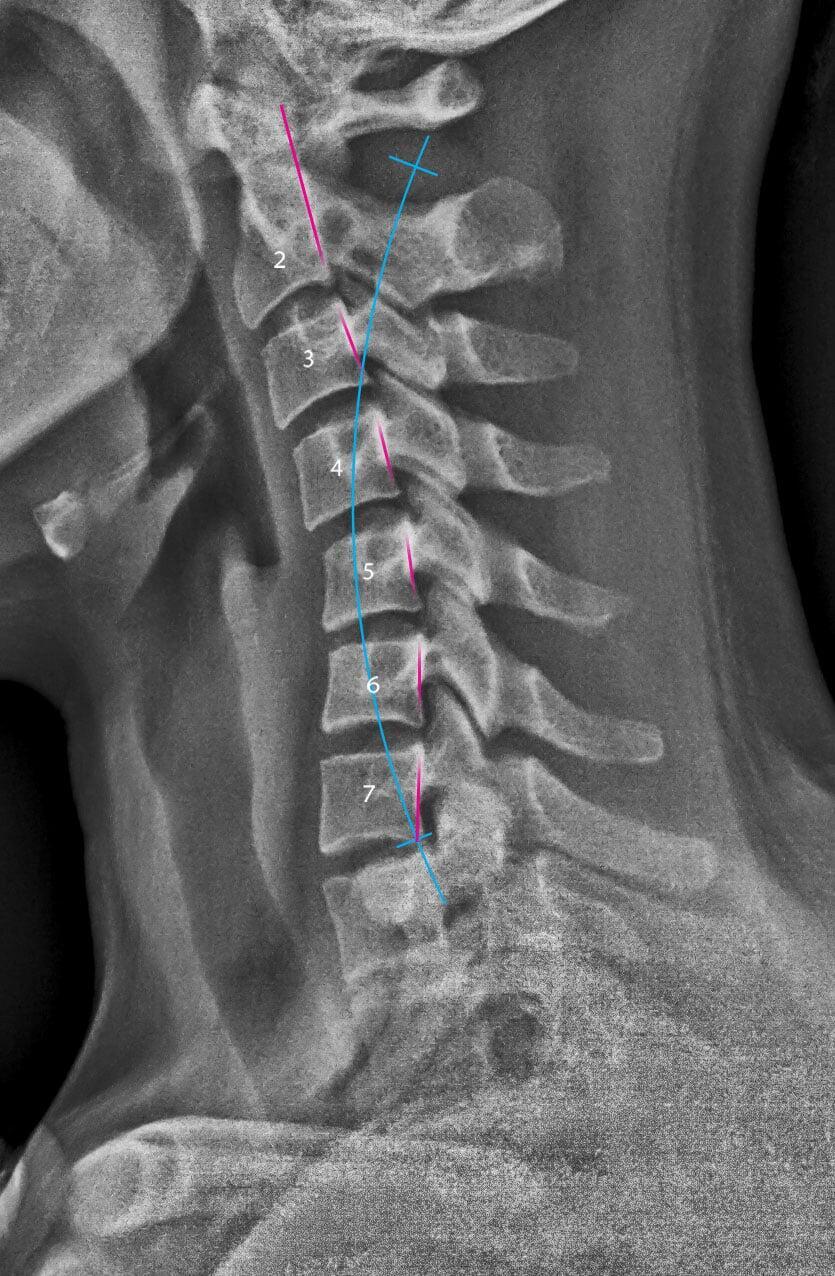

- Military spine

Your spine is designed to stay healthy your entire life. Spinal misalignments damage the spine and shorten its life. Called subluxations, these misalignments put pressure on your nervous system.

With subluxations, your brain is unable to communicate with your body, leading to health issues that come from poor function and repair.